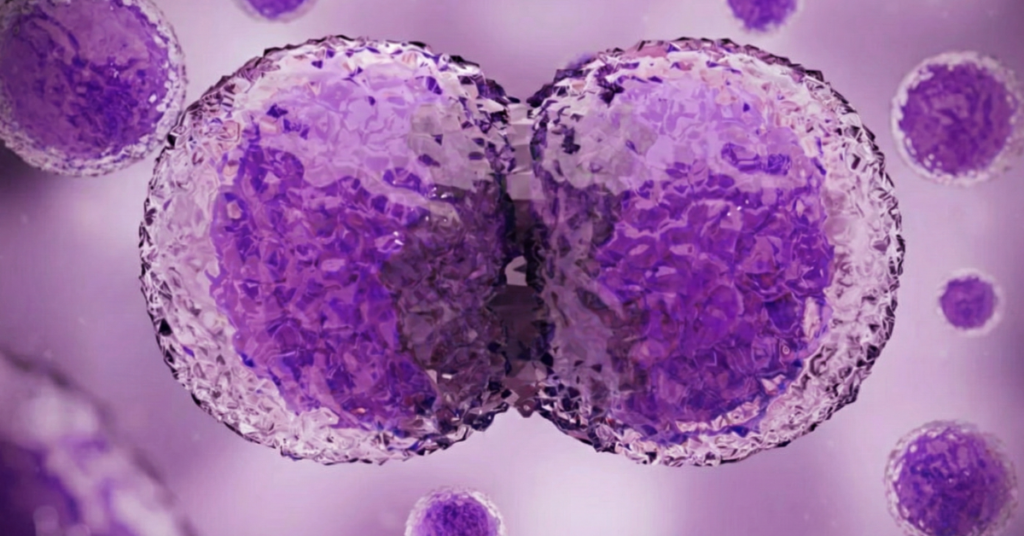

Svaka buduća mama razmišlja i proživljava svaki sekund, svaki bebin minut dok je u stomaku. Do skoro je teško bilo i zamisliti kako uopšte izgleda razvoj tog malog života, no savremene tehnologije sada to menjaju.

To čudo prirode, otelotvoreno u nastanku života tokom 40 nedelja, moguće je sada videtu u kratkom video-snimku u trajanju od četiri minute. I bukvalno se vidi svaki detalj, sve te fantastične promene na trudnici, ali i u njoj – od začeća pa do porođaja.

Tih promena mame obično nisu ni svesne, katkad traju bezgranično, ali kada se ceo taj period sažme u samo četiri minuta, rezultat je impresivan i apsolutno nikoga neće ostaviti ravnodušnim.